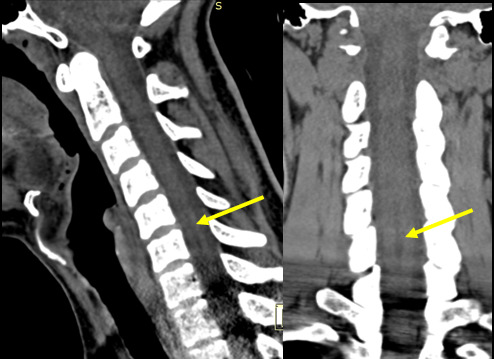

The initial CT (Figure 1) was taken in 2013. He then received intermittent physical therapy and chiropractic care from various providers from 2013-2019 for his headaches and neck pain, with little improvement seen. Due to lack of improvement, in 2016, an MRI of the cervical spine was performed (Figure 2) which revealed a fluid-filled dilatation in the central canal consistent with syringomyelia at C5-C7 measuring 26mm x 4mm x 5mm. Retrospective review of the CT study shows a subtle hypoattenuation in the central cord at C5-C7 indicating the syrinx was present at the time of the accident. In 2019, a subsequent MRI (Figure 3) demonstrated no significant change in the size or shape of the syringomyelia. In 2021, the patient gradually noticed an improvement in the frequency and duration of his headaches and dizziness. A final MRI was performed (Figure 4) which revealed a complete resolution of the syringomyelia. The patient continues intermittent chiropractic care for other unrelated complaints.